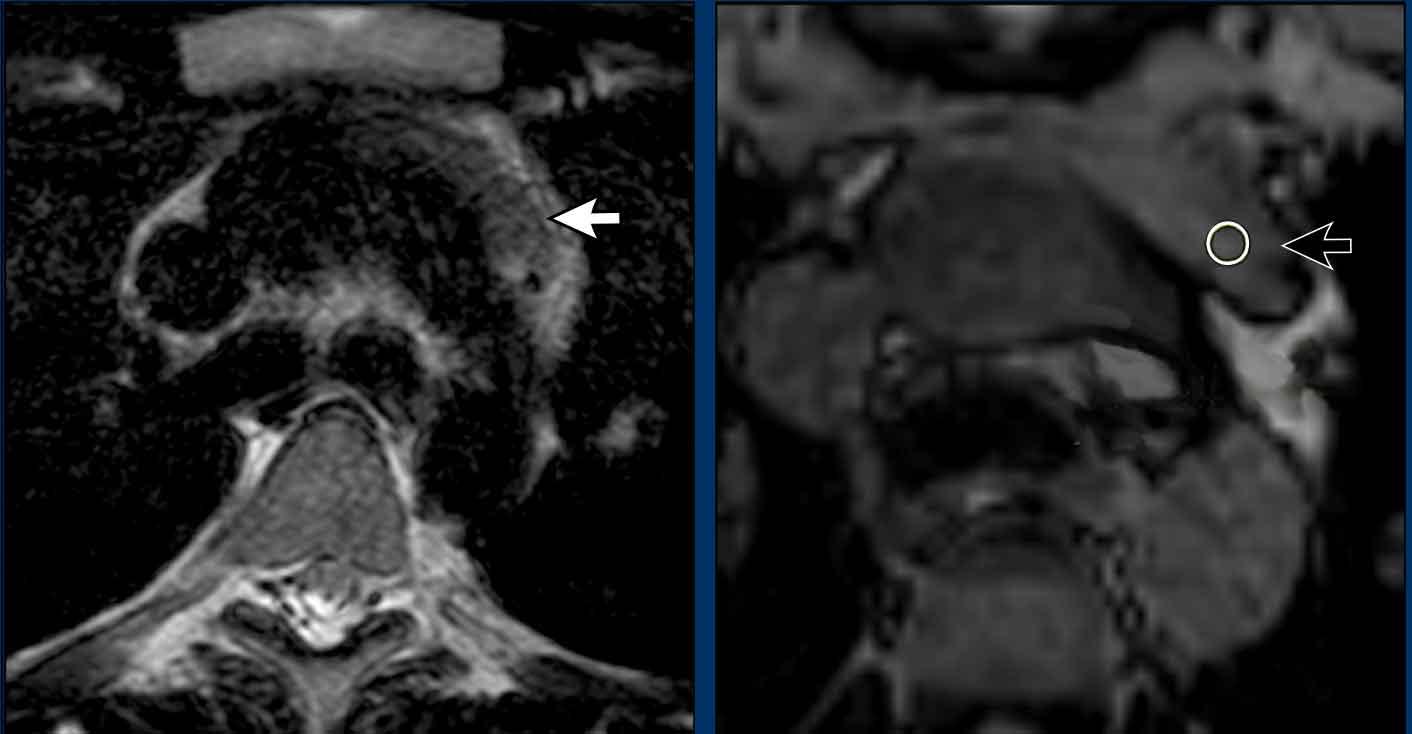

Các hình ảnh này của một nam giới 19 tuổi, được chụp CT để loại trừ thuyên tắc phổi.

Phát hiện tình cờ một khối ở khoang trước mạch máu.

Chẩn đoán có khả năng nhất là tăng sản tuyến ức và MRI được thực hiện để phân biệt thêm khối này.

Tiếp tục xem hình ảnh MRI…

Trên hình ảnh chuỗi xung T2W, tổn thương có tín hiệu tăng nhẹ.

Trên hình ảnh pha đối (out-of-phase), không có sự sụt giảm tín hiệu đáng kể.

SII nhỏ hơn 9%.

Do bệnh nhân không có bất kỳ triệu chứng nào, đặc biệt không có các triệu chứng có thể liên quan đến u lympho, và vì u tuyến ức (thymoma) là một khối u hiếm gặp, quyết định được đưa ra là theo dõi sau sáu tháng.

Tại thời điểm theo dõi sáu tháng, tuyến ức có hình ảnh bình thường.

Kết luận được đưa ra là đây là tăng sản tuyến ức hoặc mô tuyến ức tồn dư kích thước lớn, đã thoái triển trong vòng sáu tháng.